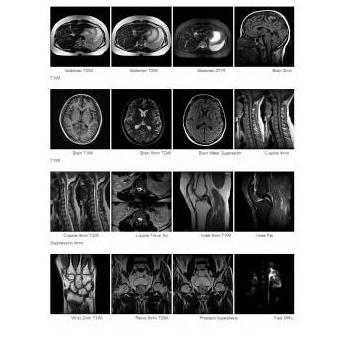

Rezonans magnetyczny MRI OPENMARK III 0.3T

Rezonans magnetyczny OPENMARK III 0.3T posiada konstrukcję otwartego magnesu w kształcie litery C, co daje większy komfort pacjentom podczas badania. Aparat dostarcza wysokiej jakości obrazy, zawiera wiele protokołów ustawiania presetów, jak również zaawansowanych aplikacji, takich jak obrazowanie dyfuzji, ultraszybkie obrazowanie, angiografia czy skanowanie na wstrzymanym oddechu.

• Pełne uaktualnienie FSE;

• Szybka technika hydrografii dla uzyskania wyraźnego obrazowania MRCP i MRU;

• Zdjęcia FOV zapewniają wysoką rozdzielczość przy obrazowaniu małych narządów;

• Skanowanie na wstrzymanym oddechu eliminuje ruch klatki piersiowej i brzucha;

• Pojedyncze zdjęcia przy ultraszybkim badaniu;

• MRA dla zastosowań klinicznych;

• Echo Sharing zmniejsza czas skanowania.